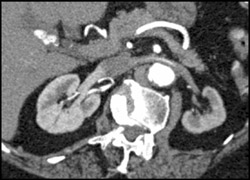

Diagnosis

Endoluminal View